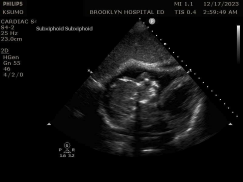

A 46-year-old female with a prior medical history of asthma presented to the emergency department with shortness of breath and wheezing. After three DuoNeb treatments and 16 mg of dexamethasone, her wheezing improved; however, she continued to report shortness of breath on exertion. Given the persistent symptoms, a cardiac point-of-care ultrasound was obtained.

ACEP Now: Vol 43 – No 12 – December 2024Findings showed an irregularly shaped mobile heterogeneous echo-texture mass within the left atrium and a similar yet larger structure in the right atrium (see figures 1 and 2). Consequently, a CT chest angiogram was performed that confirmed the cause of her cardiac wheeze: a large bilobed mass, involving the right and left atrium, that appeared to extend through a large atrial septal defect (see figure 3).